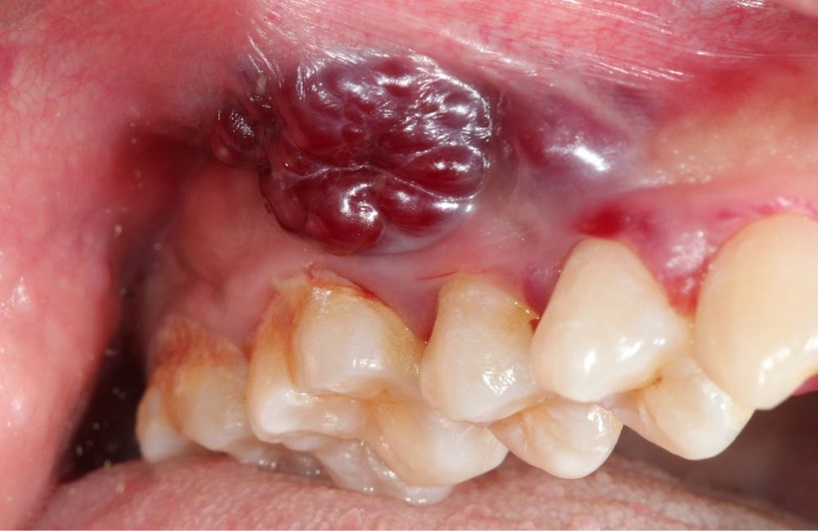

Cysts and growths in the oral region are present in different forms and can develop themselves on the tongue, the gums, the palate or inside the cheeks or beneath the jaw. Some of the common ones include the mucoceles (fluid-filled sacs commonly caused by clogged salivary glands), fibromas (noncancerous growth of connective tissue) and periapical cysts (periapical cysts are associated with infected or dead teeth). Other growths may turn out to be more severe such as precancerous lesions or cancers of the mouth.

- Ulceration or bleeding: Any oral lesion which bleeds for no particular reason at all or which fails to heal completely in the period of two weeks must be inspected as it may indicate some worse malaise.